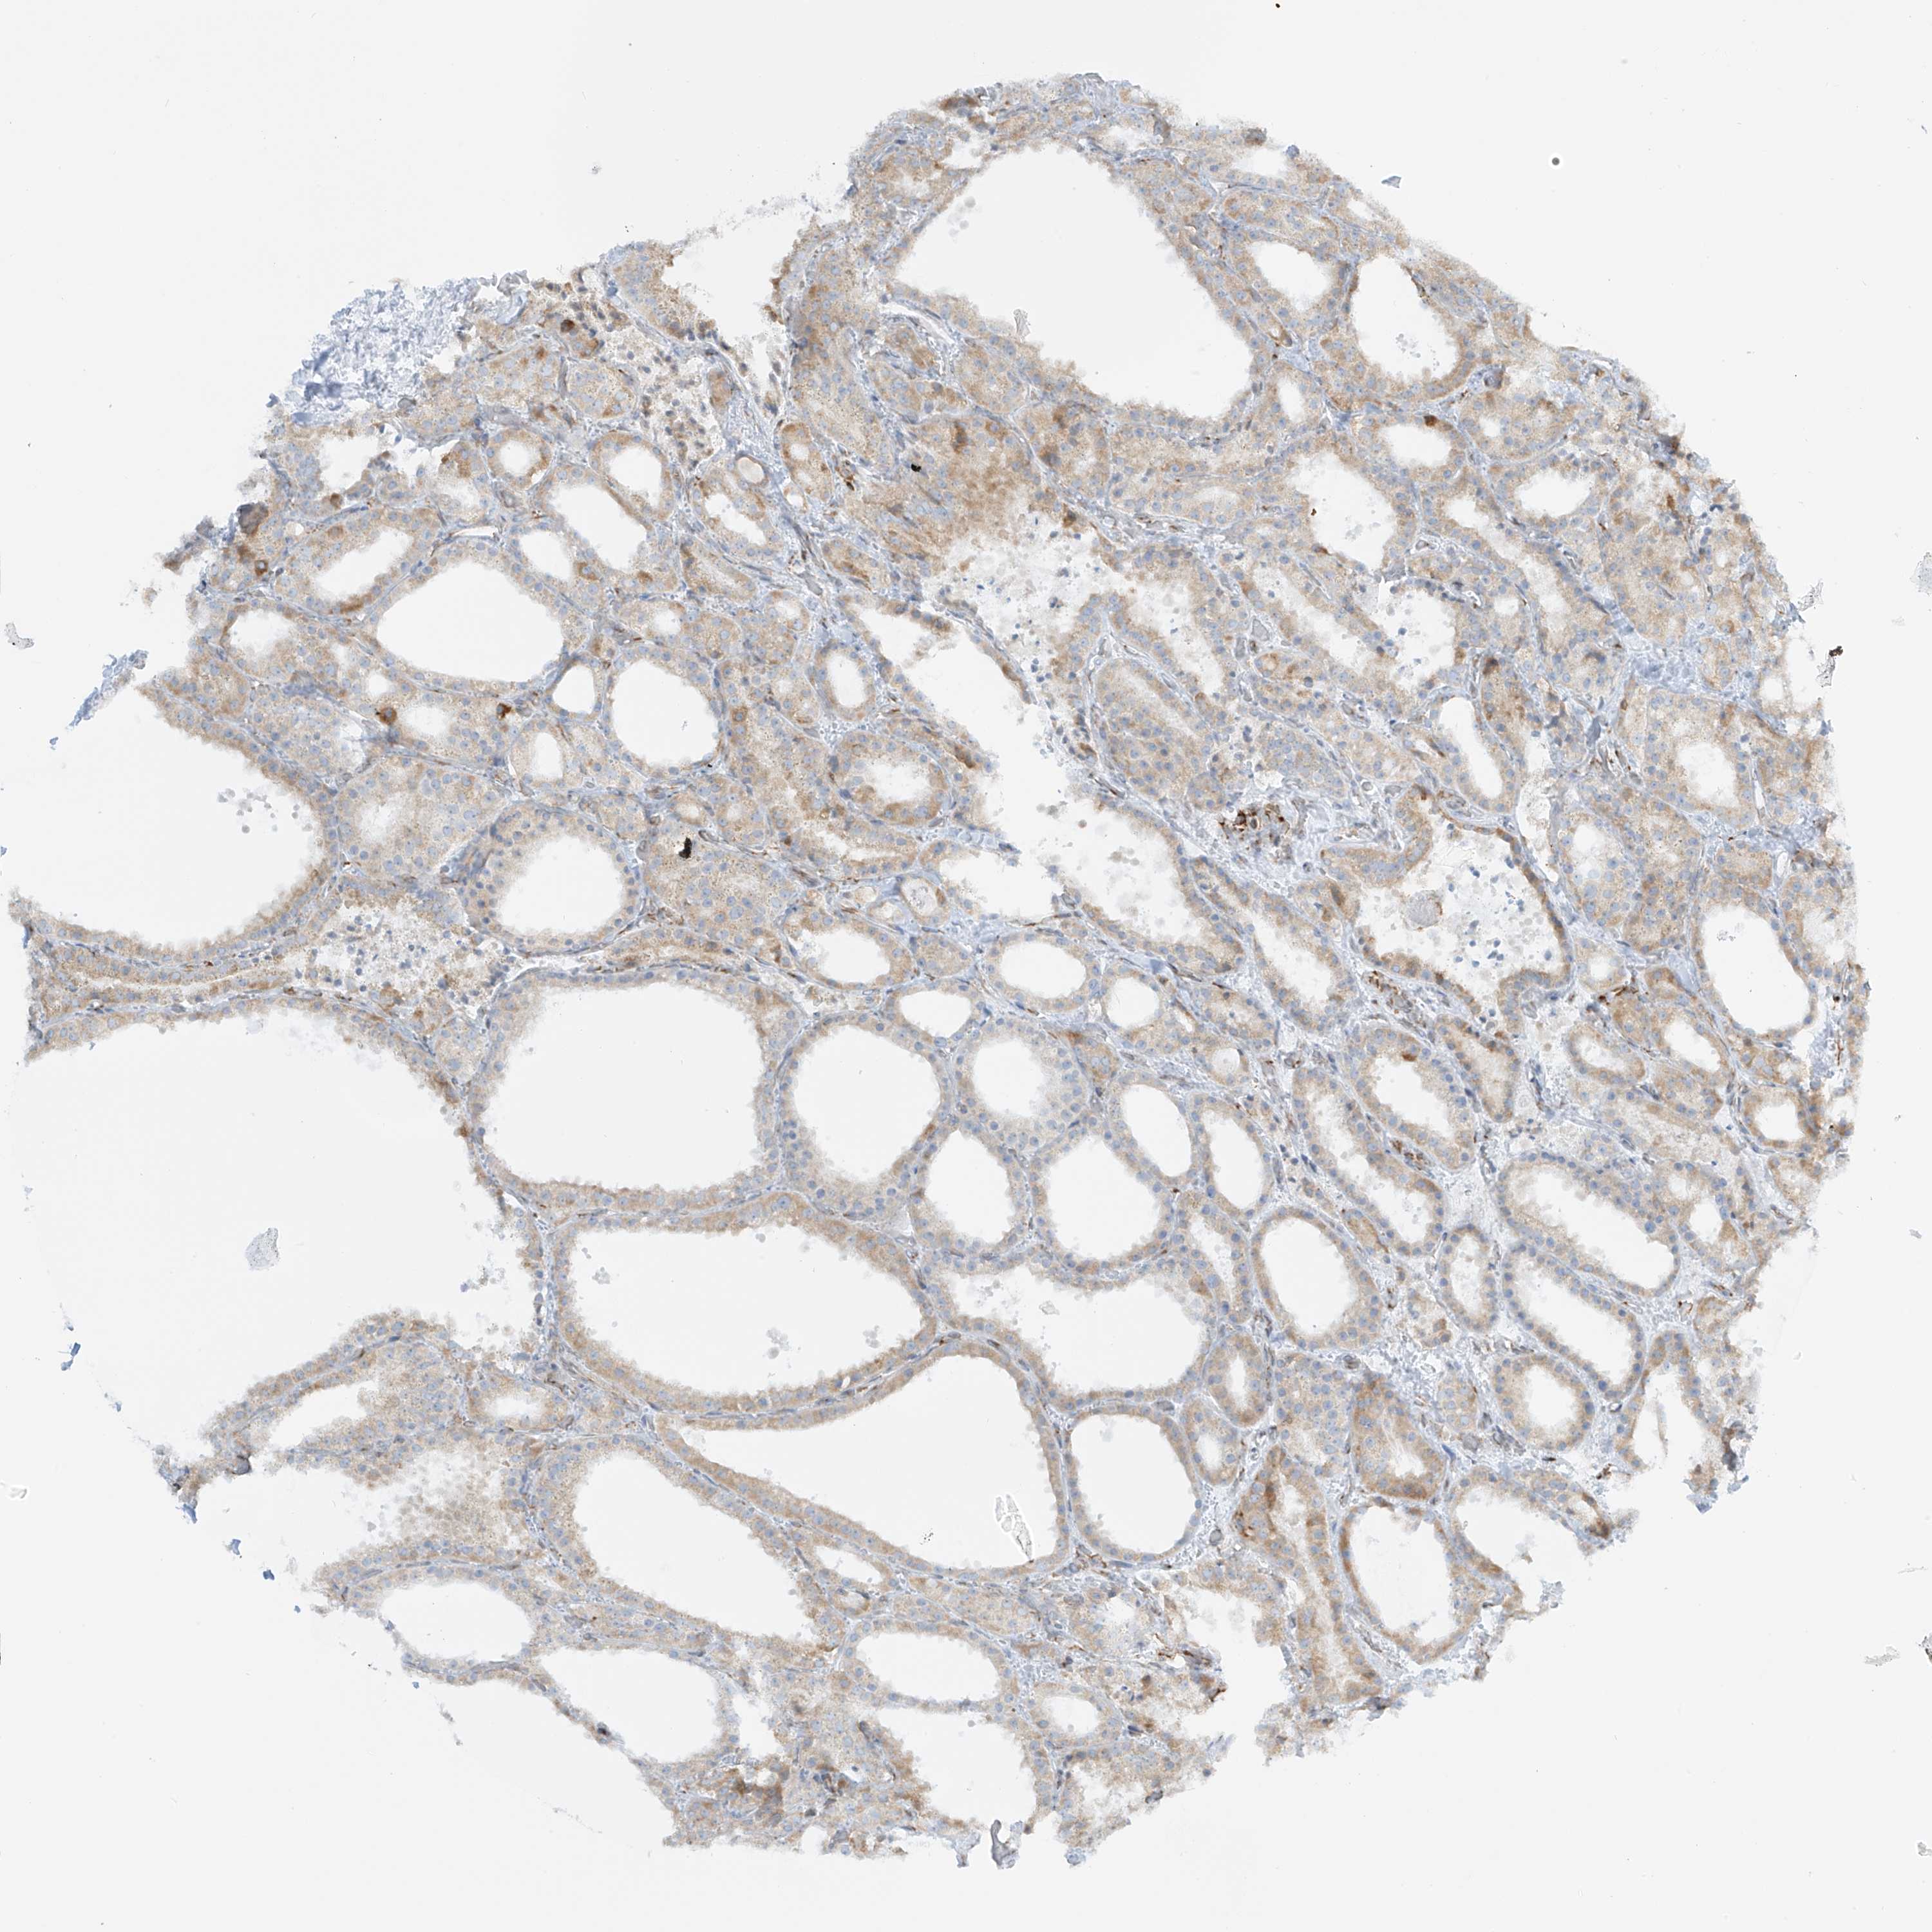

THYROID CANCER - Protein expressioni

A mouse-over function shows sample information and annotation data. Click on an image to view it in a full screen mode. Samples can be filtered based on level of antibody staining by selecting one or several of the following categories: high, medium, low and not detected. The assay and annotation is described here.

Note that samples used for immunohistochemistry by the Human Protein Atlas do not correspond to samples in the TCGA dataset.

Antibody stainingi

Antibody staining in the annotated cell types in the current human tissue is reported as not detected, low, medium, or high, based on conventional immunohistochemistry profiling in selected tissues. This score is based on the combination of the staining intensity and fraction of stained cells.

Each image is clickable and will lead to virtual microscopy that enables deeper exploration of all samples and also displays staining intensity scores, fraction scores and subcellular localization as well as patient and tissue information for each sample.

Antibody HPA030827

Antibody HPA030829

Staining

High

Medium

Low

Not detected

Intensity

Strong

Moderate

Weak

Negative

Quantity

>75%

75%-25%

<25%

None

Location

Nuclear

Cytoplasmic/membranous

Cytoplasmic/membranous,nuclear

Papillary adenocarcinoma, NOS

Follicular adenoma carcinoma, NOS